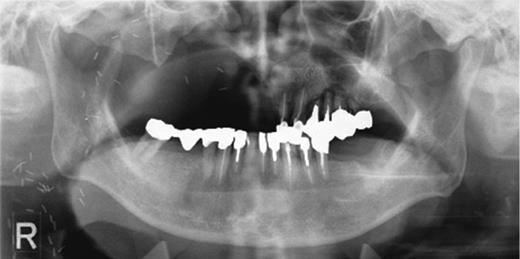

Preoperative orthopantomography. Molar teeth on the left side had been previously extracted because of severe periodontitis.